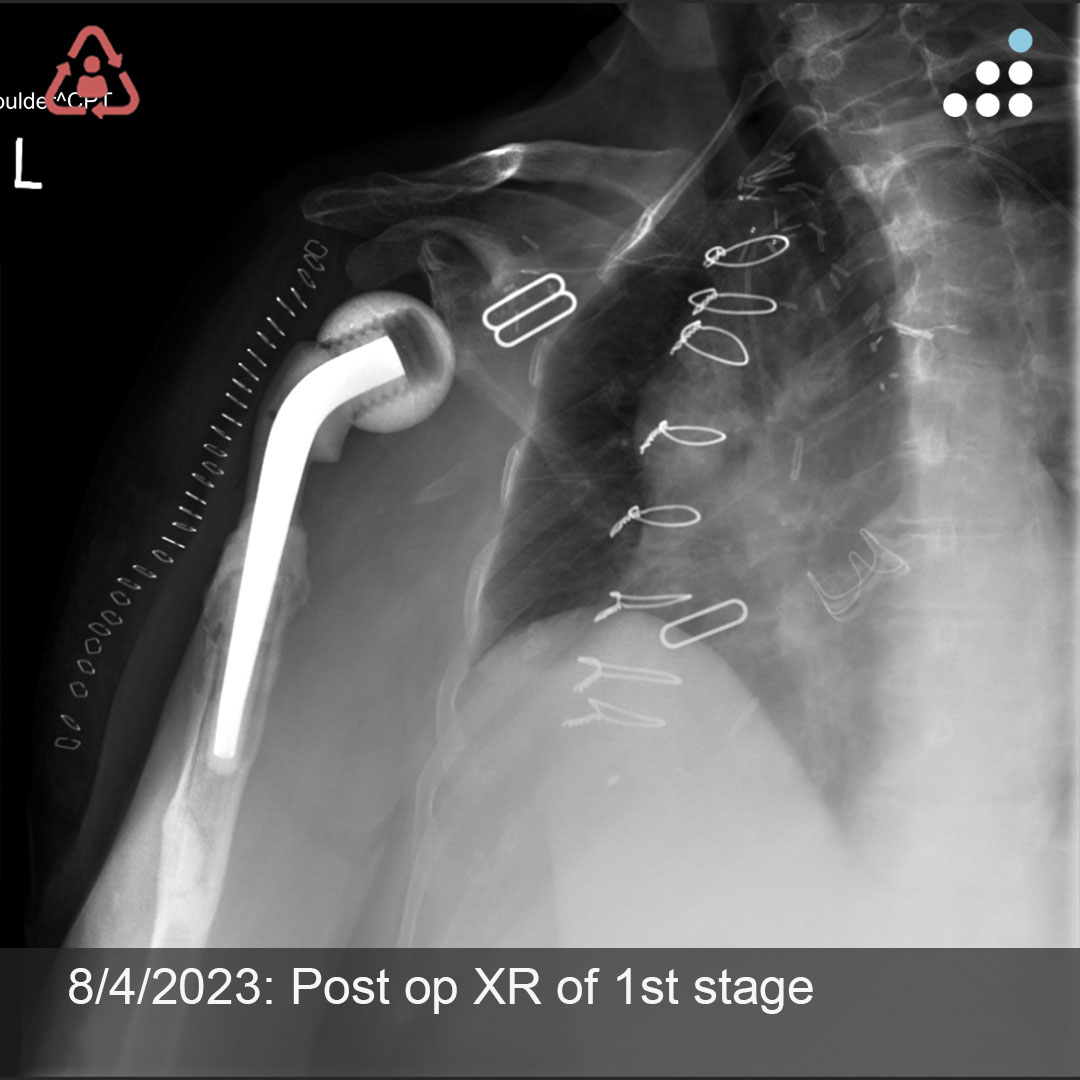

@orthobullets If there is still some cartilage left on the reverse Hill Sachs I’ve had some luck with doing a humeral head osteoplasty. I’ll use allograft chips or cement to backfill the defect after I tamp up articular surface and then try to get everything repaired especially in young pts